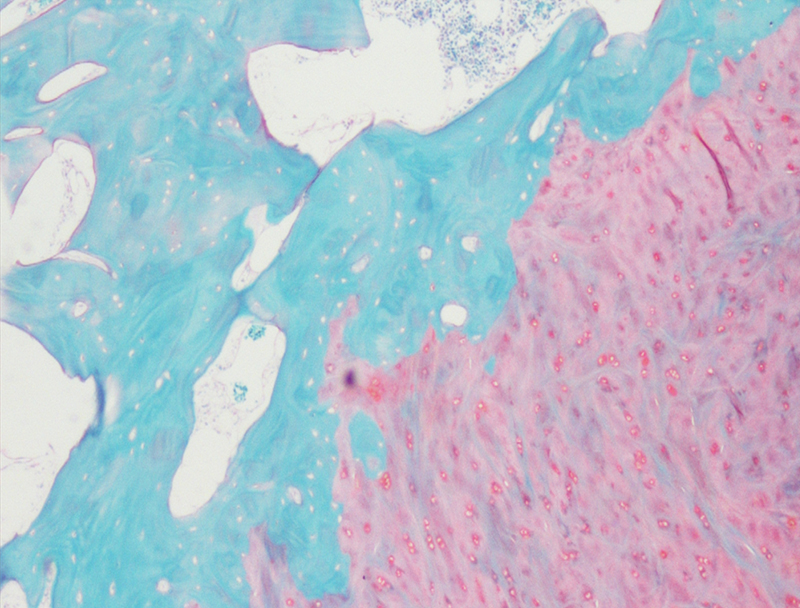

Masson染色

番红固绿染色